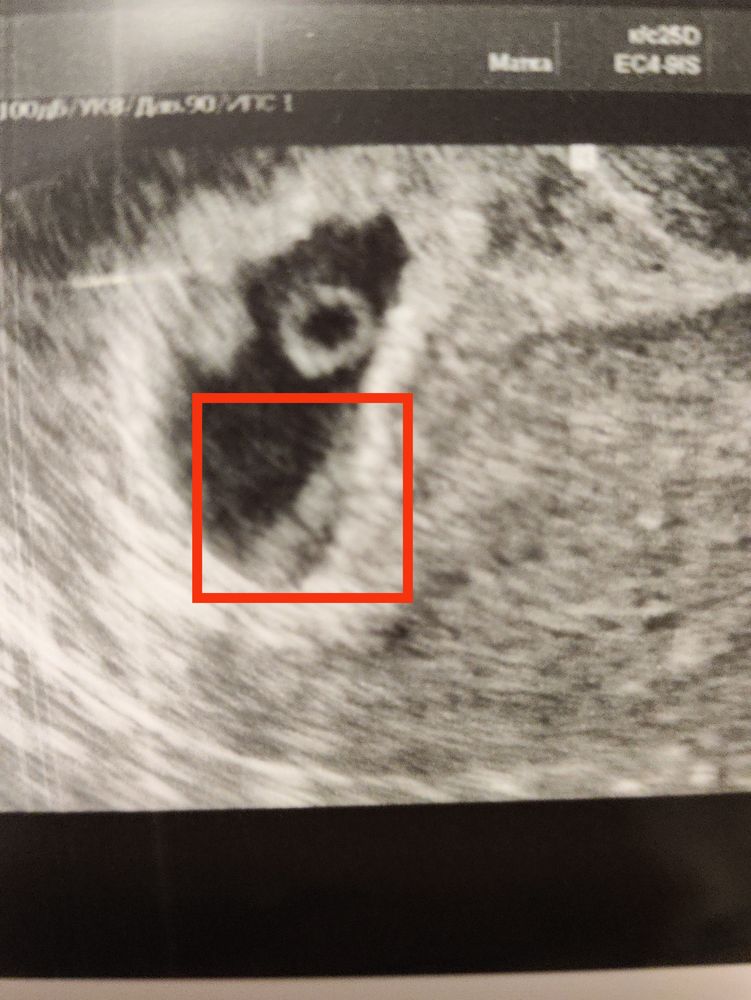

В заключении написала, что по внутренним контурам ПЯ амниотический тяж, хотя на УЗИ говорила, что перегородка (но это может одно и то же, не поняла).

Вот на фото, на УЗИ вот это сказала, что перегородка.